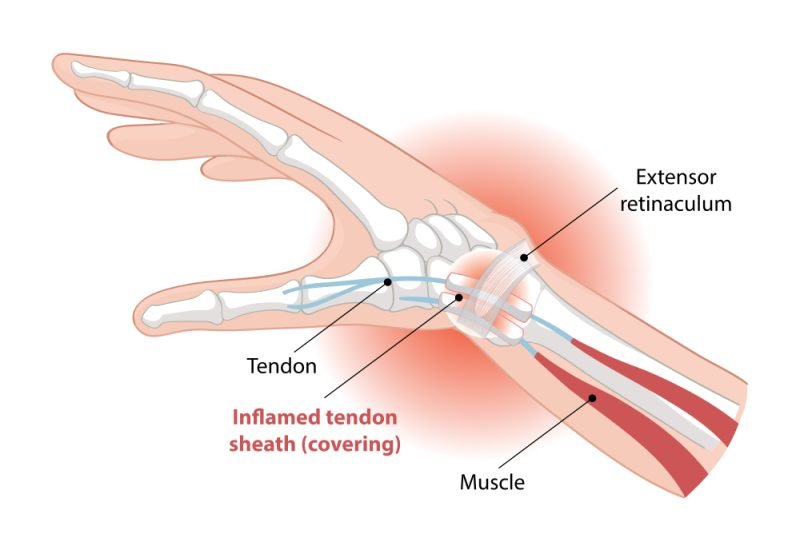

Tendinitis

Wrist and Hand

The injuries of the wrist or hand in gymnastics, basketball, or falls are fractures, sprains, and tears of the ligaments. Injury can be minimized through proper technique and strengthening.